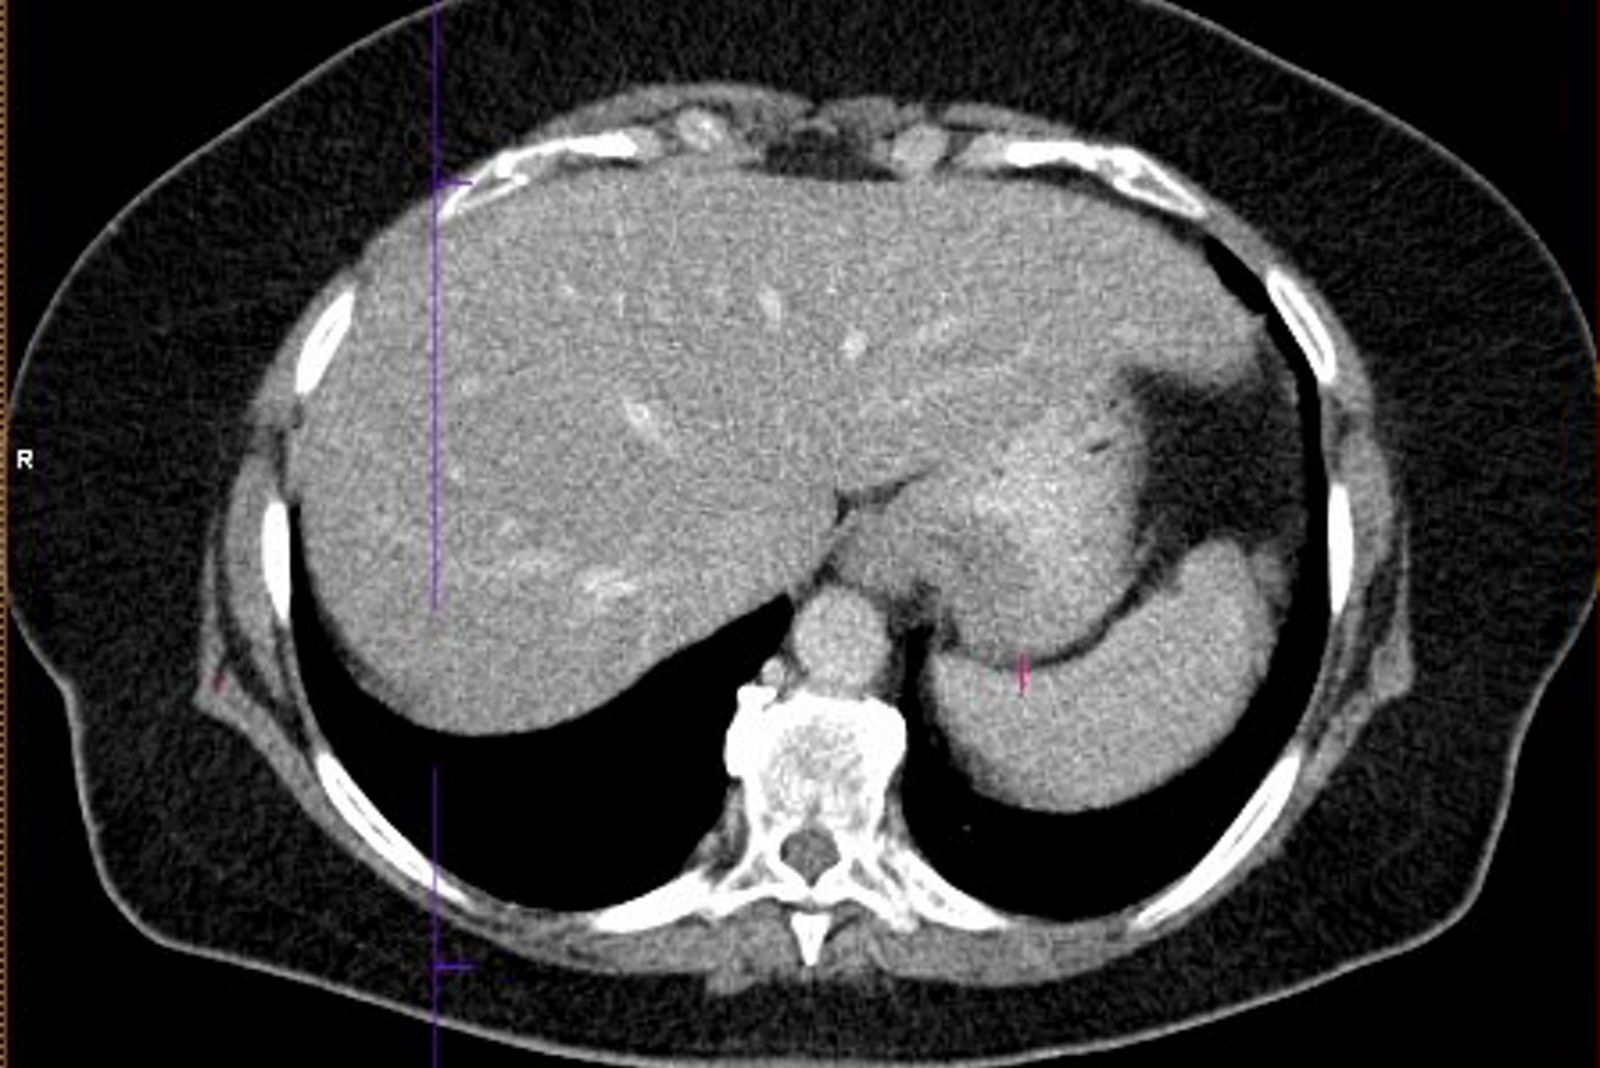

Die PET-CT-Untersuchung ist eine kombinierte nuklearmedizinisch-radiologische Bildgebung, eine Positronenemissionstomographie kombiniert mit Computertomographie. Sie stellt auf der einen Seite Stoffwechselveränderungen dar, auf der anderen Seite morphologische Veränderungen.

Meist wird mit F-18 markierte Glukose verwendet, um die Verteilung des Glukosestoffwechsels darzustellen, es können aber auch z.B. Rezeptor gerichtete Substanzen verwendet werden. Im CT-Teil der Untersuchung werden die morphologischen Verhältnisse dargestellt, je nach Fragestellung und Vorbefunden mit diagnostischer CT oder als Niedrig-Dosis-CT.

Kolorektale Karzinome haben in der Regel einen deutlich gesteigerten Glukosestoffwechsel, d.h. sie können in der PET-CT durch eine vermehrte Speicherung des verwendeten Radiopharmakons nachgewiesen werden. Auch Metastasen eines kolorektalen Karzinoms weisen diesen erhöhten Glukosestoffwechsel auf.

In der Beurteilung möglicher Fernmetastasen kann die PET-CT wertvolle Zusatzinformationen liefern, die die primäre Therapie beeinflussen können, z.B. bei der Beurteilung von Lungenrundherden unklarer Dignität, die Lungenmetastasen entsprechen oder aber auch Zweitmalignomen oder narbigen Veränderungen entsprechen könnten.

Auch kann vor Resektion von resektablen Lebermetastasen die PET-CT mit dem Ziel der Vermeidung einer unnötigen Laparotomie durchgeführt werden. (S3-Leitlinie Kolorektales Karzinom)